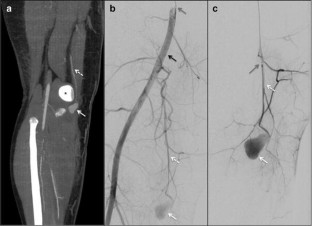

Ten patients (mean age 55.1 years) have been treated for arterial embolization using MVP; eight extracranial and two intracranial arterial embolizations have been performed. The embolizations were because of: four bleedings, three aneurysms, two pseudoaneurysms, and one presurgical nephrectomy.

MVP3 was used in five cases, MVP5 in four cases, and MVP 7 once. In all cases, the MVP was successfully released in < 1 min. In six patients, the MVP was the sole embolizing agent employed, while in four subjects, it was positioned complementary after coils. The technical and clinical success was obtained in 100%; hemorrhages were interrupted and aneurysms and pseudoaneurysms did not show recanalization at follow-up.